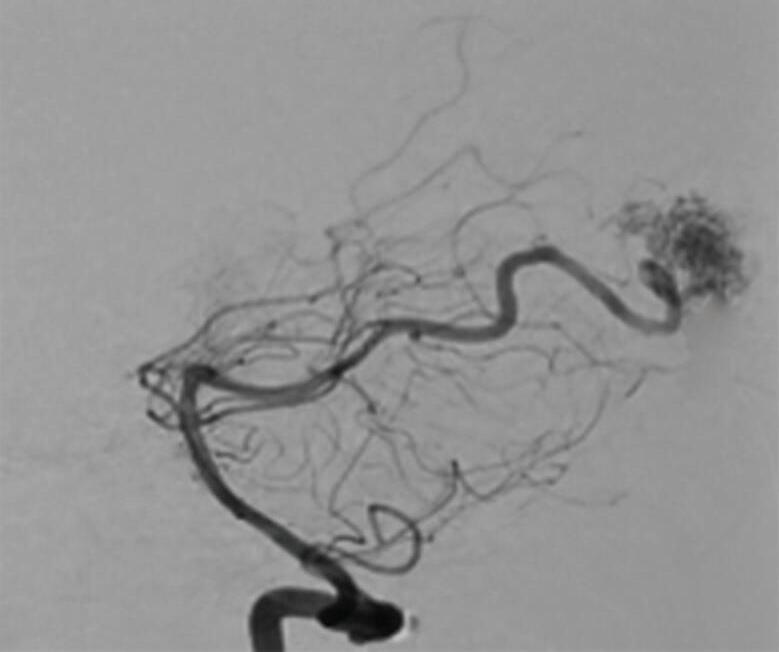

Fig. 1-8. (a-c) RNM T1 com contraste, cortes sagital (a), coronal (b) e axial (c) demonstrando MAV não rota com nidus localizado no lobo occipital à esquerda (setas longas). (d) Arteriografia digital cerebral com injeção de contraste via carótida direita (AP) mostrando a contribuição da carótida direita na irrigação da MAV contralateral. (e,f) Com injeção de contraste via carótida esquerda, em Perfil e AP respectivamente, observa-se nidus compacto nutrido por ramos da artéria cerebral média à esquerda e a veia de drenagem precoce se dirigindo para o seio sagital superior. Projeções em AP (g) e em perfil (h) demonstrando a contribuição do sistema vertebrobasilar por meio de ramos distais da artéria cerebral posterior à esquerda e drenagem para os seios sagital superior e sigmoide à esquerda (setas curtas).

Fig. 1-9. RNM T2 em cortes (a) axial e (b) sagital. (c,d) Tractografia axial – sagital, demonstrando a posição de uma MAV não rota localizada na superfície basal do lobo frontal, nos giros orbitários e reto à direita (setas longas). Arteriografia digital cerebral com injeção de contraste via carótida direita, (e) AP e (f) em perfil demonstrando MAV nutrida por ramos da artéria cerebral média e cerebral anterior direita e drenagem para o seio sagital superior (seta curta).